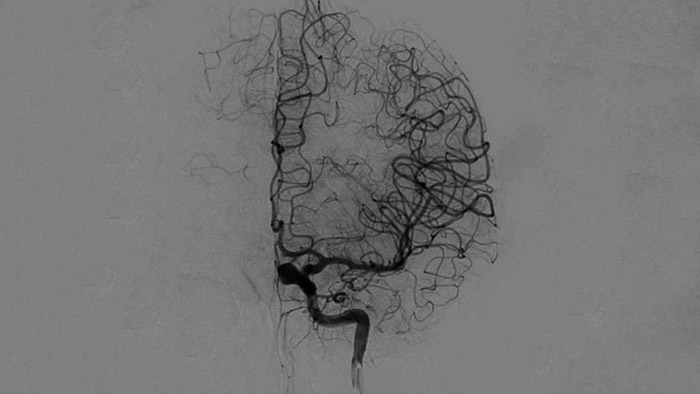

Imágenes nítidas con ASD 2D con tecnología ClarityIQ

ASD 2D con tecnología ClarityIQ

ClarityIQ aplica la compensación automática del movimiento durante la ASD en tiempo real para mantener imágenes nítidas de los vasos. Esto permite tomar decisiones con confianza durante los procedimientos para atender accidentes cerebrovasculares.

Confirmar el éxito del tratamiento

Visualización de la ASD

Las visualizaciones de la ASD de alta calidad le permiten evaluar si ha recuperado el coágulo completo y si los trozos de coágulo se han dispersado distalmente en el cerebro. Puede comprobar el restablecimiento del flujo sanguíneo en la penumbra y comprobar si hay hemorragias periprocedimiento.